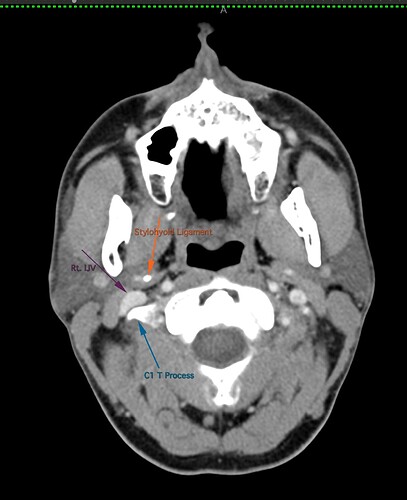

So, 2 years ago was the first time I came across Living with Eagle, filled with descriptions of all my symptoms, and a slew of scans showing very obvious bone chunks in the neck. Since I studied bio in college, and these bones are obvious, I figured I’d take a stab at looking at my own past scans and, low and behold, mild–but present–ossification of my stylohyoid ligament. Perhaps more relevant in my case, in the process of learning enough of the anatomy to understand axial images I noticed another weird thing–my right external carotid artery is in the wrong place. Instead of sitting lateral to my hyoid greater cornu, it’s medial. Hmm.

Tonsil surgery did solve the problem of my tonsils hurting, because they were gone, but no resolution of other symptoms. This was a year ago. I’ve been to PT, SLP, and now back to PT while I trial gabapentin for the neurologist. PT#2 discovered a bunch of significant atrophy in my upper right shoulder/back, and, you guessed it it’s all right sided. I’ve since then, thanks to radiopedia and Netter’s, also explored my images and noticed a few other anomalies in my scans, including an extended right thyroid superior cornu which appears to be pressing strongly into my neck also in the general area of pain, and an occipital artery branching off and wrapping around the internal carotid. Frustratingly these also weren’t mentioned on rads reports. My swallow study by the SLP showed obvious asymmetry with my swallow, but the SLP reported it symmetric and radiology apparently doesnt read the A/P view in their modified barium swallow studies? This is not inspiring faith in the academic institution I attended, but what can I possibly know they dont?